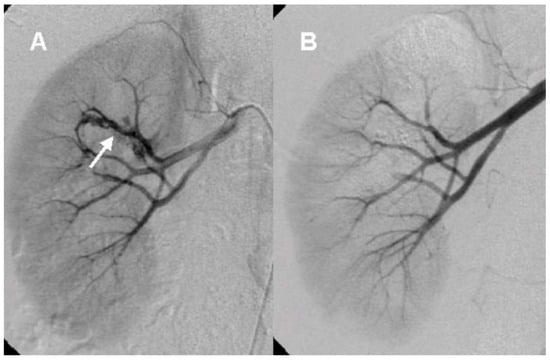

In the current study, we confirmed the following characteristics of renal AVM described in previous studies. Almost all patients presented with gross hematuria (12 patients, 92.3%). The most common type of AVM was cirsoid (10 patients, 76.9%). The right kidney was more frequently involved than the left (right: 9 patients, 69.2%) [14]. All patients were women. Congenital renal AVM is a female-predominant disease according to the published case reports, though there are a few reports of AVM in men [8,15]. The age of patients was from 30 to 40 years old, demonstrating that their mean age was 36.9 years [16]. Four (30.8%) patients were related with pregnancy [16]. TAE is a safe and effective treatment of renal AVM demonstrating a success rate of 91.7% in our results [7]. Based on our findings and diagnostic clues, we developed an algorithm for the diagnosis of renal AVM (Figure 4).

According to our diagnostic clues, hematuria in 30–40-year-old woman with history of recent pregnancy or delivery, and no apparent cause of hematuria on conventional imaging study is strongly suggestive of renal AVM. Gross hematuria from the ureteral orifice may also be a clue for renal AVM during cystoscopy. Furthermore, duplex color Doppler US is an important non-invasive diagnostic tool for renal AVM.

Figure 4. The diagnostic clues for renal arteriovenous malformation.